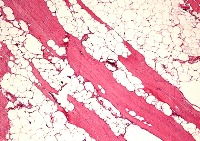

Adipose Tissue

Skeletal Muscle